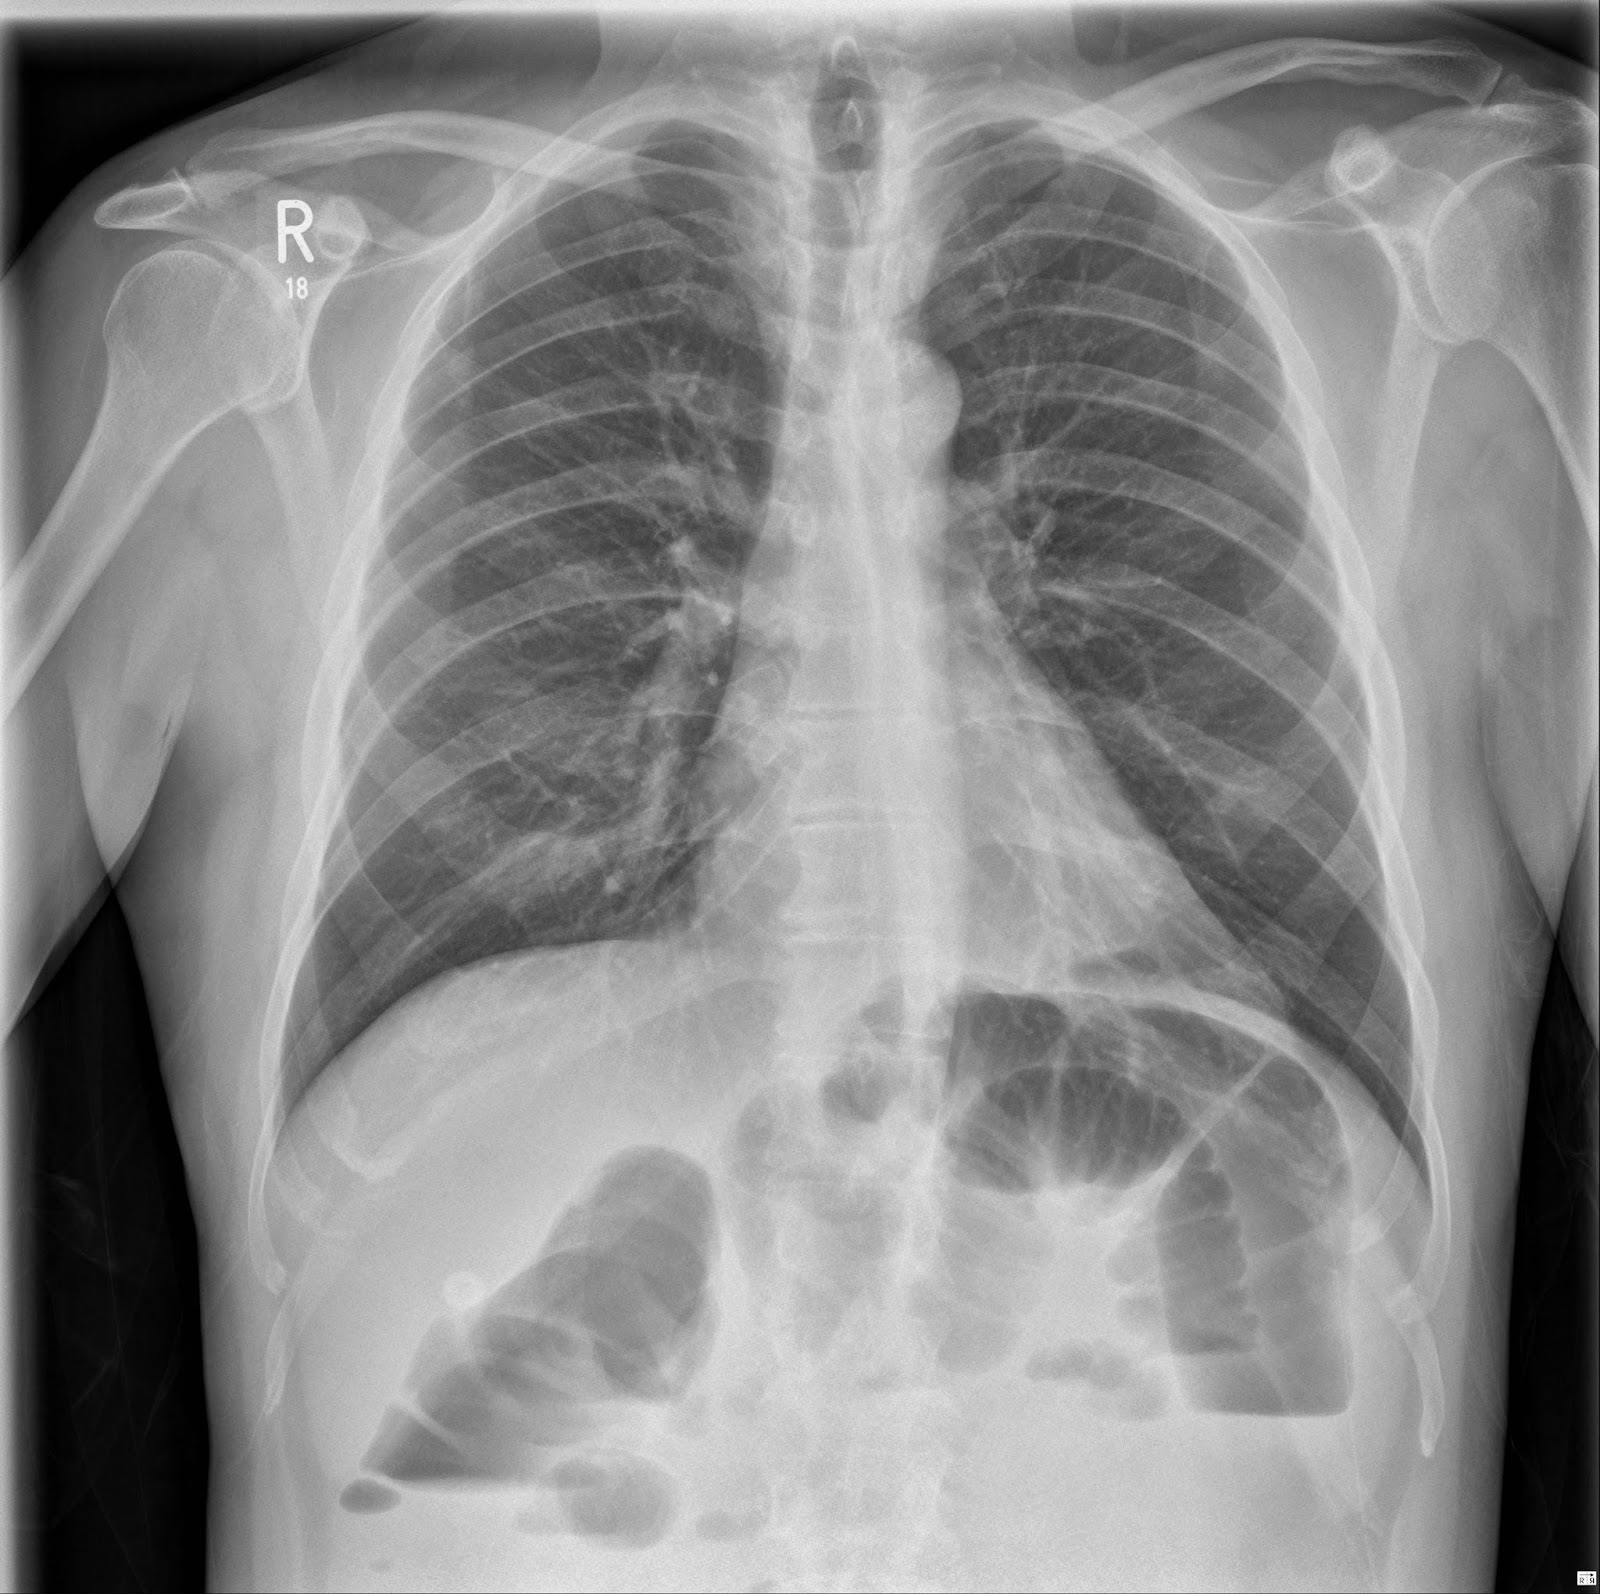

From www.stepwards.com

Interpreting An Abdominal XRay (KUB) Stepwards Does A Chest X-Ray Show Pancreatitis The web page explains the 2012 revised atlanta. Acute pancreatitis is a sudden and severe inflammation of the pancreas that causes abdominal pain, nausea, fever and jaundice. Pain consistent with acute pancreatitis) lipase / amylase. This can help identify a cause or rule out other problems. Acute pancreatitis is usually diagnosed in hospital, where you'll receive treatment and be monitored. Does A Chest X-Ray Show Pancreatitis.